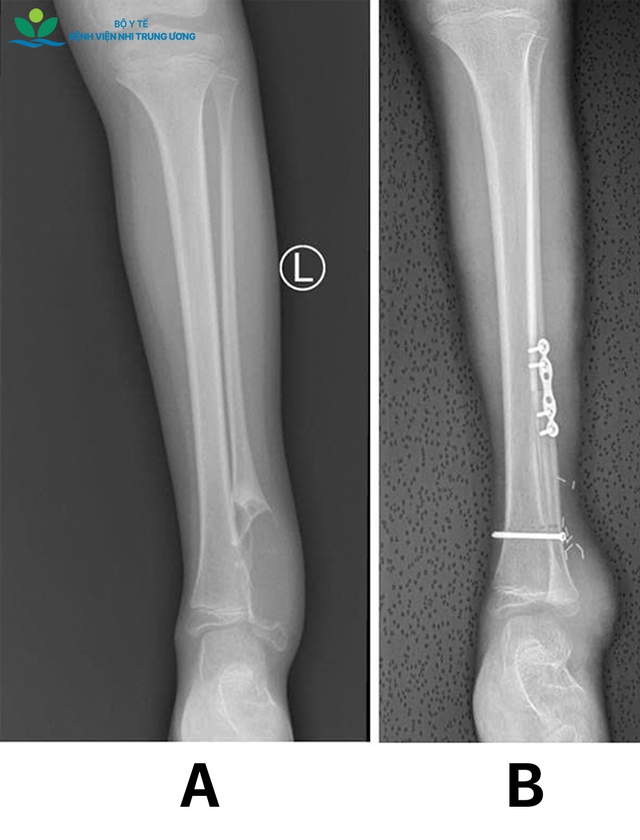

Kết quả thăm khám và chẩn đoán hình ảnh cho thấy khối u Chondrosarcoma (u sụn ác tính) tái phát ở đầu dưới xương mác bên trái (toàn bộ mắt cá ngoài bị tổn thương), kích thước lớn, chèn ép sát các cấu trúc mạch máu và thần kinh quan trọng vùng cổ chân. May mắn, các kiểm tra chuyên sâu xác định bệnh chưa di căn các cơ quan khác. Các bác sĩ đã tiến hành cắt bỏ toàn bộ khối u đầu dưới xương mác trái theo nguyên tắc ung thư xương, giải phẫu bệnh cho kết quả diện cắt âm tính (R0) - điều kiện then chốt để giảm nguy cơ tái phát tại chỗ.

Hình ảnh X quang: (A) trước mổ cắt u; (B) sau mổ ghép vạt xương